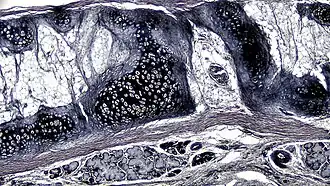

![]() A cross section of mammalian elastic cartilage | |

Elastic cartilage is histologically similar to hyaline cartilage but contains many yellow elastic fibers lying in a solid matrix. These fibers form bundles that appear dark under a microscope. The elastic fibers require special staining since when it is stained using haematoxylin and eosin (H&E) stain it appears the same as hyaline cartilage.[3] Verhoeff van Geison stains are used (giving the elastic fibers a black color), but aldehyde fuchsin stains, Weigert's elastic stains, and orcein stains also work.[3] These fibers give elastic cartilage great flexibility so that it is able to withstand repeated bending. Similarly to hyaline one or multiple chondrocytes lie between the spaces (or lacunea) in the fibres.[2] The chondrocytes only make up 2% of the tissue's volume.[2] Chondrocytes and the extracellular matrix are contained in an outerlayer named the perichondrium[2] (which is a layer of dense irregular connective tissue that surrounds cartilage which is independent of the joint).[3] It is found in the epiglottis (part of the larynx), and the pinnae (the external ear flaps of many mammals). Elastin fibers stain dark purple/black with Verhoeff's stain.